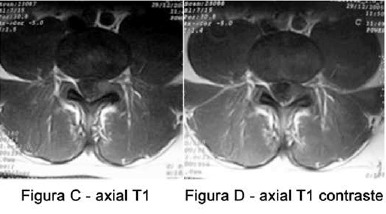

Um paciente de 55 anos apresentou início de lombalgia em 04/2004, quando realizou exame de RM que revelou alterações degenerativas (Figura A). Ele relata que, no final de 2005, a dor mudou de características e passou a irradiar para o MIE, tendo realizado novo exame de RM (Figuras B, C, D).

Após a análise das imagens de RM acima, o diagnóstico da causa da dor do paciente é: